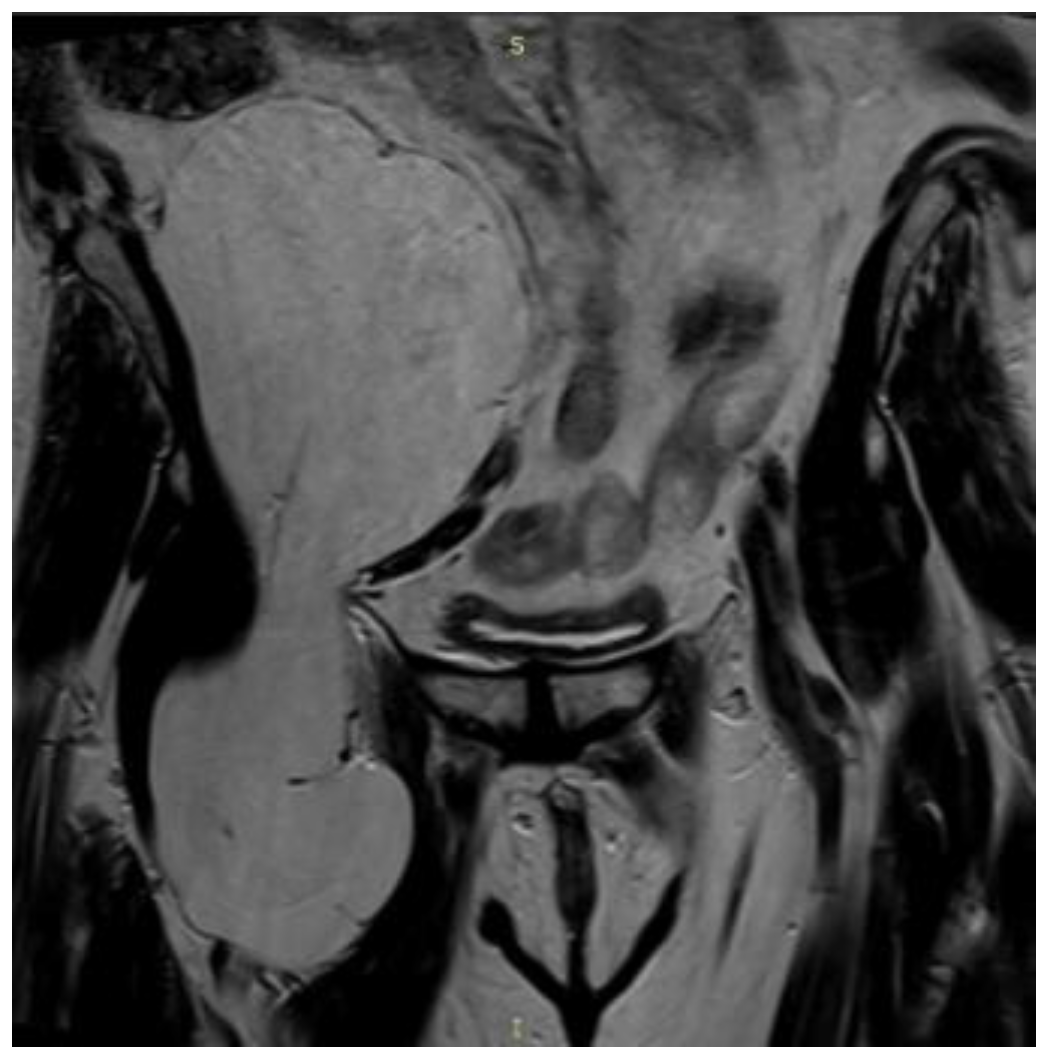

2. Case Presentation